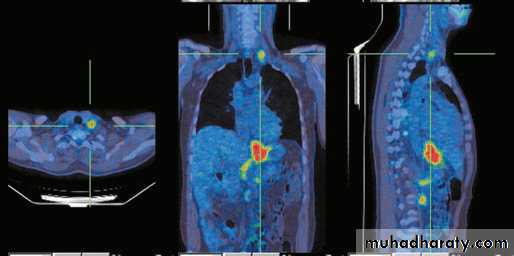

Figure5: EUS showing early tumorPET scan

Fiagure6: pet scan showing a tumor and distant metastasis.